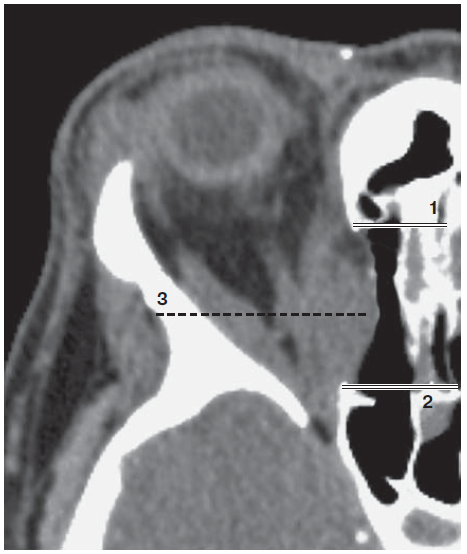

1. Рис.2. Компьютерная томография пациентки после ТЭДО, аксиальный срез. Отмечены границы наложенного костного окна (1,2); пролабирование орбитальных тканей в сформированное костное окно (3) | |

4. Рис. 2. Компьютерная томография пациентки после ТЭДО. Аксиальный срез. Отмечены границы наложенного костного окна (1, 2); пролабирование орбитальных тканей в сформированное костное окно (3). | |